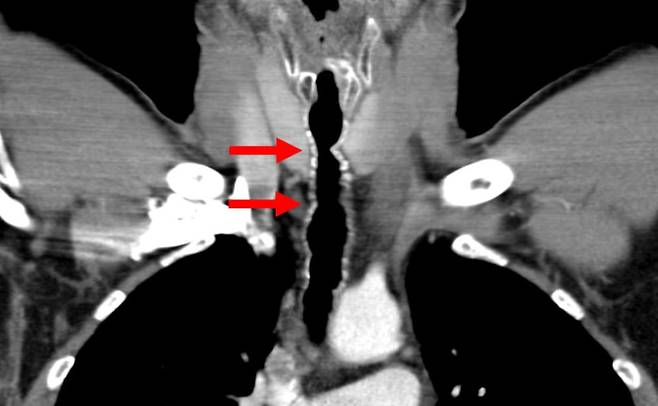

기관지 내시경 검사 결과 A씨의 과거 목 안에 수술했던 부위에서 염증과 여러 개의 털이 자라나는 것이 확인됐다. A씨는 기관 내 모발 성장, 즉 목구멍에 모발이 자라는 진단을 받았다.

의료진은 A씨가 10살 때 익사할 뻔했고, 응급처치로 후두가 손상된 후 기관절개술을 받은 점에 주목했다. 상처 부위는 귀의 피부와 연골을 자가 이식했는데, 털이 자란 것은 이 부위였다. 의사들은 털을 뽑아 제거했지만 이는 일시적인 해결책에 불과했다.

머리카락은 계속 자라났고, 환자는 같은 증상을 호소하며 10여년간 매년 병원을 찾아야 했다. A씨의 목에는 약 5cm 털이 6~9개가 반복적으로 자라났고 일부는 성대를 지나 입으로 뻗어 나갔다. 이 털이 박테리아로 덮여 있었기 때문에 항생제 치료까지 받아야 했다.